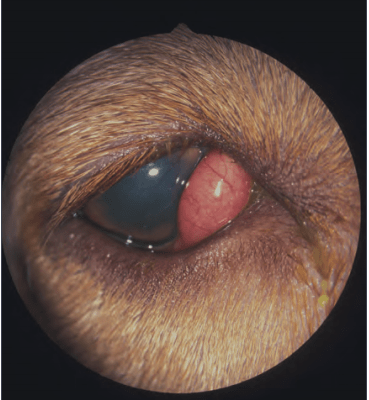

狗的泪腺脱垂特写.樱桃眼

纯种斗牛犬,樱桃眼,第三眼睑外翻